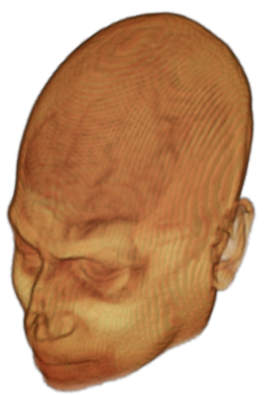

To prevent these types of attack, medical scans are currently de-identified using crude removal-based techniques [Bischoff-Grethe et al.(2007)Bischoff-Grethe, Ozyurt, Busa, Quinn, Fennema-Notestine, Clark, Morris, Bondi, Jernigan, Dale, Brown, and Fischl, Schimke et al.(2011)Schimke, Kuehler, and Hale, Milchenko and Marcus(2013)] which seek to remove privacy-sensitive parts of the head (examples in Figure 3). However, as we demonstrate, these existing techniques fail to reliably hide the patient’s identity – or they are so aggressive that they impair further medical analyses. A better solution is needed.

A handful of de-identification techniques exist for MRI scans, which are conventionally used for sharing and distribution of MRI data. These existing methods rely on a removal approach to privacy. DEFACE [Bischoff-Grethe et al.(2007)Bischoff-Grethe, Ozyurt, Busa, Quinn, Fennema-Notestine, Clark, Morris, Bondi, Jernigan, Dale, Brown, and Fischl] estimates the probabilities of voxels belonging to the face based on an atlas of healthy control subjects. The scan is de-identified by setting intensities of voxels whose probabilities are small enough to zero. QUICKSHEAR [Schimke et al.(2011)Schimke, Kuehler, and Hale] is a fast but simple approach that computes a hyperplane to divide the MRI into two regions: one containing facial structures, and the other containing the brain of the scan. Voxels in the first part are set to zero. FACE MASK [Milchenko and Marcus(2013)] uses a filtering method to blur the facial features. These existing de-identification approaches are based on traditional computer vision techniques; we believe that the proposed algorithm is the first to adopt a learning-based approach.

Benchmark De-Identification Methods. We compare our result with three publicly available and widely-established methods for de-identification of MRI head scans, depicted in Figure 3. All methods have in common that they (1) are not deep-learning-driven, (2) require no additional training and (3), are used on a day-to-day basis in neuroscience and clinical research. All procedures were applied with default settings on images of resolution . The methods include QUICKSHEAR [Schimke et al.(2011)Schimke, Kuehler, and Hale], FACE MASK [Milchenko and Marcus(2013)], and DEFACE [Bischoff-Grethe et al.(2007)Bischoff-Grethe, Ozyurt, Busa, Quinn, Fennema-Notestine, Clark, Morris, Bondi, Jernigan, Dale, Brown, and Fischl]. Descriptions of the methods are provided in the Appendix. We also include MRI WATERSHED [Ségonne et al.(2004)Ségonne, Dale, Busa, Glessner, Salat, Hahn, and Fischl], a skull-stripping method that removes everything except the brain.